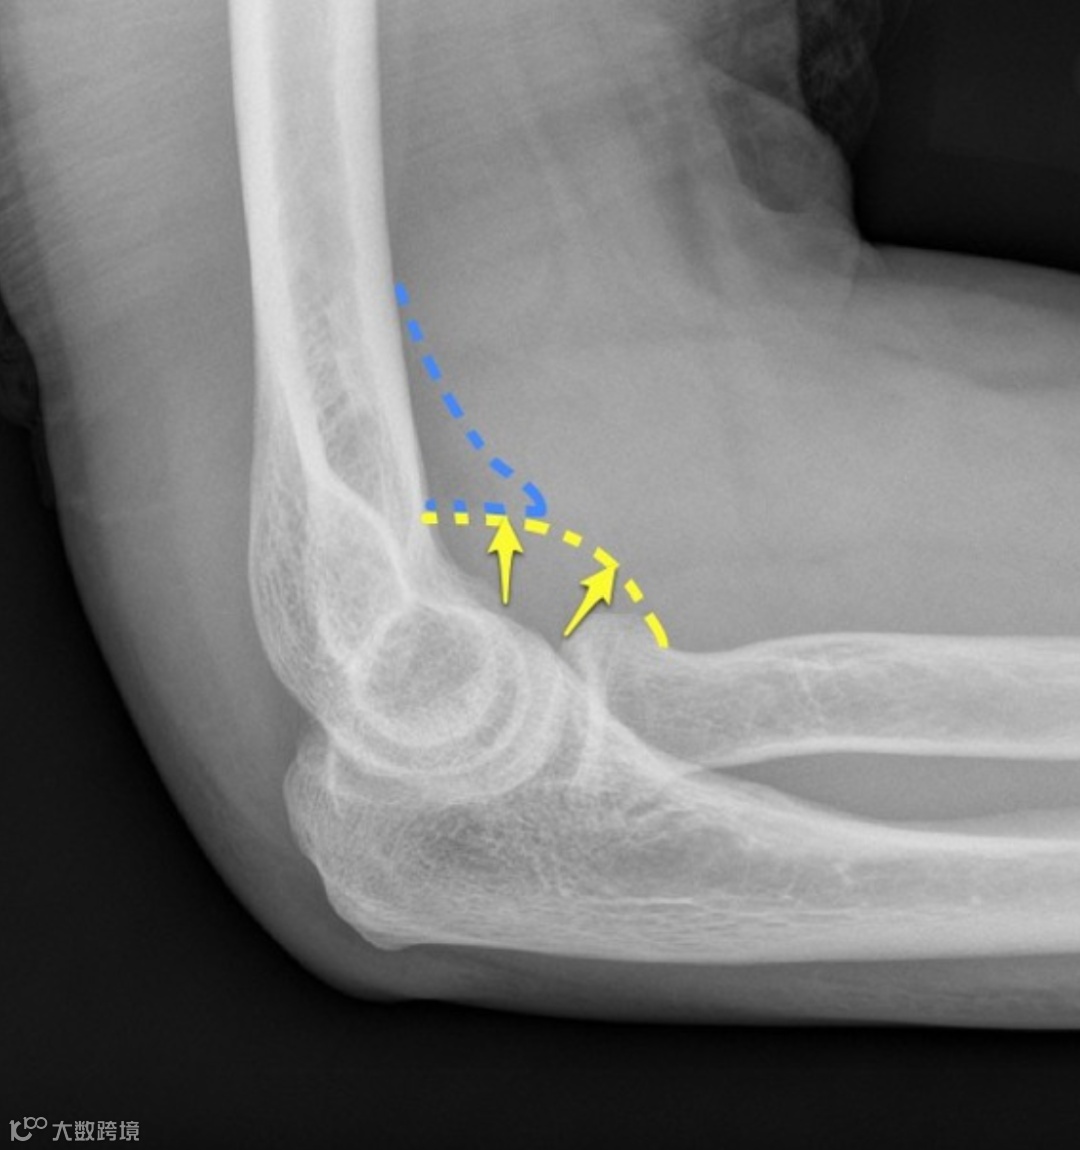

同一患者,10天后复查右肘关节,X线斜位显示持续存在的帆征(蓝色)。桡骨头前侧皮质骨缺损可见,证实关节内骨折存在,但未移位且隐匿。